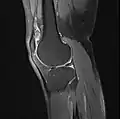

MRI

Both anterior cruciate ligament (ACL) and posterior cruciate ligaments (PCL) are hypointense on both T1 and T2 weighted images of MRI. However, some high signal striations are often seen at the distal part of the ACL, making ACL higher intensity than PCL on MRI scans.[17]

Knee MRI (PD TSE FS sagittal)

Knee MRI (T1 TSE sagittal)- Knee MRI (sagittal TSE FS)